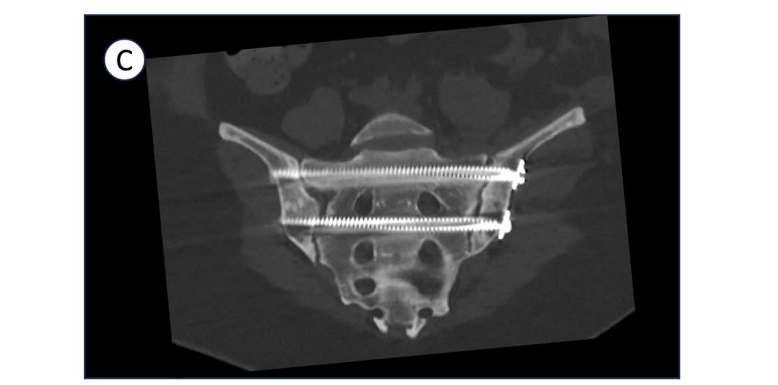

Fig. 4:术后CT扫描显示复位和螺钉轨迹

常规进行术后CT扫描以评估骨折复位和植入物位置。除非因其他损伤禁止,通常建议患者在患侧进行点地负重。首次术后随访安排在六周,进行临床和放射学评估,以检查是否有骨折移位或内固定物问题。如果对伤口愈合有任何现有担忧,则安排额外的随访。随后在三个月、六个月和一年时拍摄随访X光片,以监测骨折愈合和任何潜在的创伤后关节炎发展。